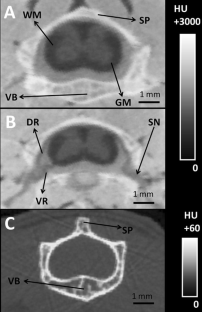

Fig. 2

GM:

Gray matter

WM:

White matter

HU:

Hounsfield units

SP:

VB:

SN:

Spinal nerve

DR:

Dorsal root

VR:

Ventral root